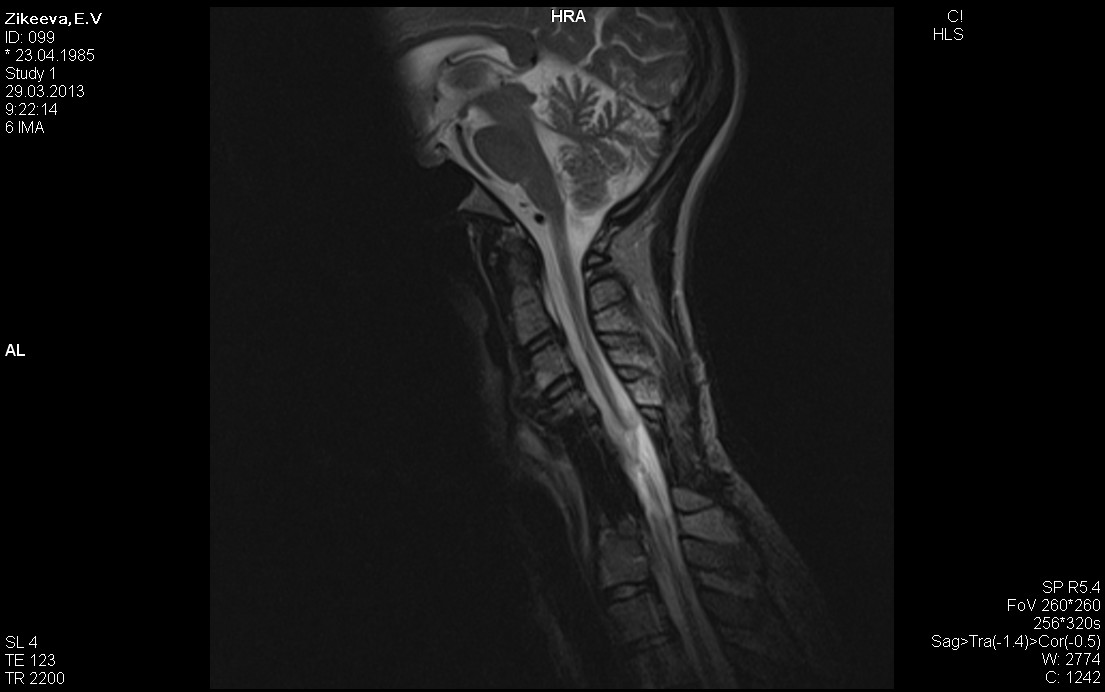

Здравствуйте! Меня зовут Елена, 31год.У меня травма шейного отдела позвоночника с5с6 с 2007 года. Сильный ушиб спинного мозга, движения в ногах отсутствуют. Каждый год прохожу лечение в санатории и реабилитационном центре. Дважды в год принимаю нейромидин и сосудистые препараты. Несмотря на это сохраняется очень низкое давление и плохое самочувствие. Скажите пожалуйста какой из препаратов лучший в моем случае для прохождения нервного импульса по спинному мозгу и где лучше консультироваться? Спасибо!